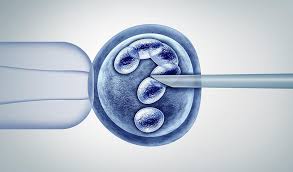

Kalıtsal Hastalık Taşıyıcılığı ve Embriyo Seçimi: Daha Sağlıklı Gebelik Şansı body { font-family: Arial, sans-serif; line-height: 1.6; ...

Tüp Bebek Öncesi Beslenme: Gebelik Şansınızı Artırın - Prof. Dr. Birol Vural Tüp Bebek Tedavisi Öncesi Nasıl Beslenmeli? Tüp beb...

Sperm Kalitesini Arttıran Besinler: Gebelik Şansınızı Artırın Sperm Kalitesini Arttıran Besinler: Gebelik Şansınızı Artırın Erke...

Düşük Yumurtalık Rezervinde Hangi Tedaviler Yapılır? - Prof. Dr. Birol Vural Düşük Yumurtalık Rezervinde Hangi Tedaviler Yapılır? ...